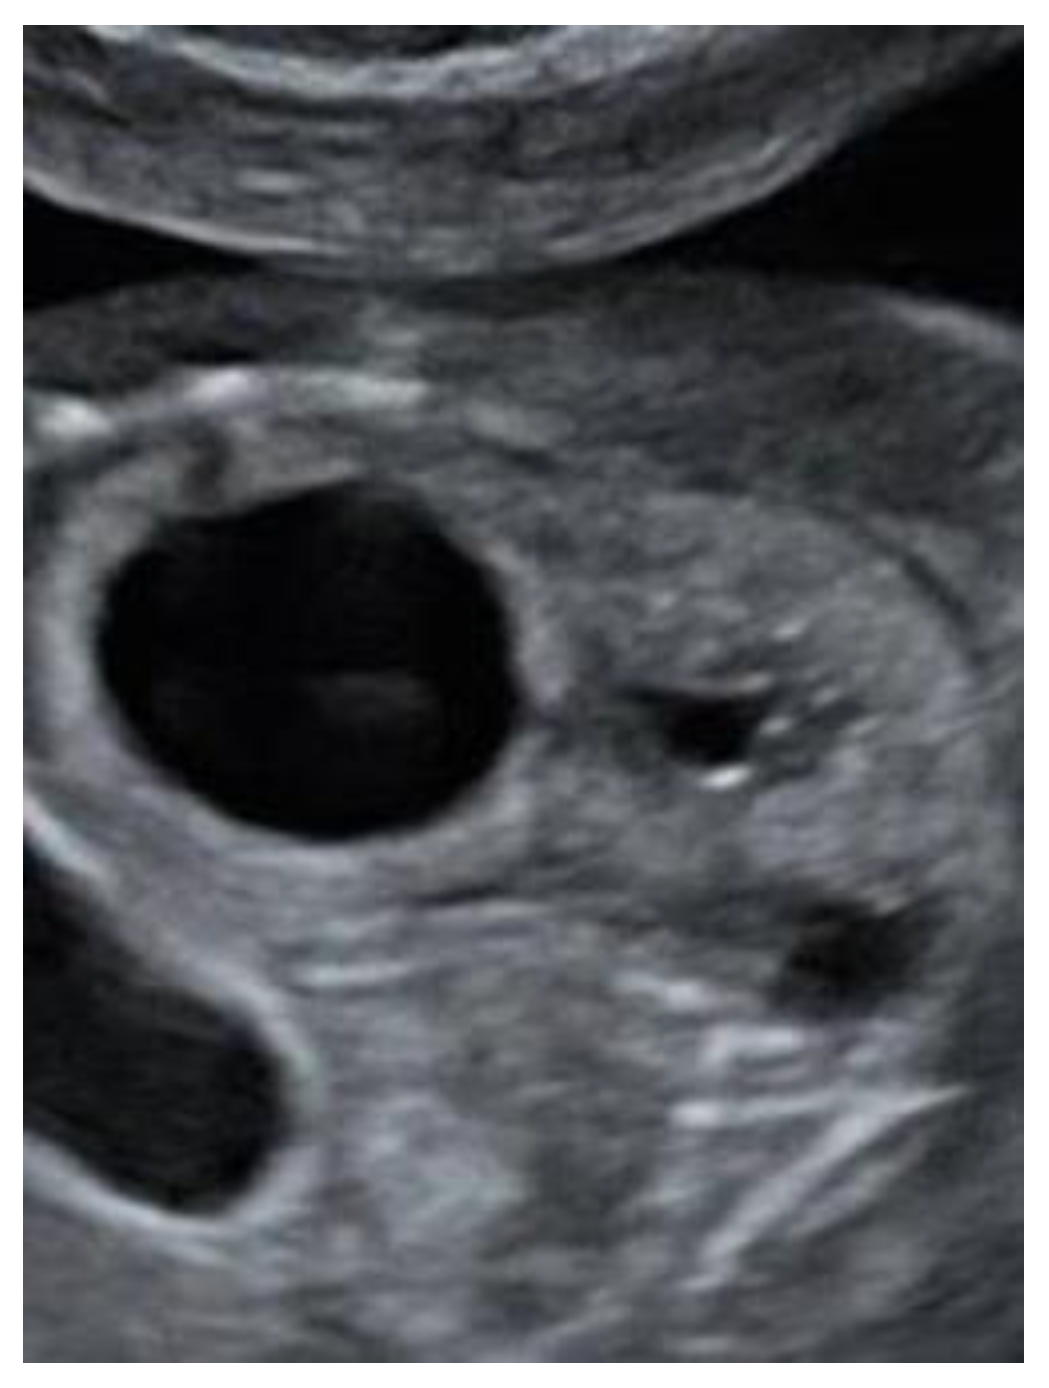

Figure 2). The lateral ventricles were not dilated. Ultrasound examination of the spine revealed a closed skin except for a minimal fistula in the sacro-coccygeal region (

Figure 3,

Figure 4 and

Figure 5). Furthermore, an abnormal gap between the second and third digit was seen on both hands as well as a syndactyly between the first and second toe. Cardiac sonography was normal at both 17- and 24-weeks GA, with a normal four-chamber view, outflow tracts, and three-vessel view. An amniocentesis was performed to rule out genetic anomalies and to measure alfa 1-fetoprotein. Additionally, a fetal MRI was carried out mainly to assess the fetal spine, as the cerebral findings all indicated the presence of an open neural tube defect. MRI analysis confirmed the hydroureteronephrosis as well as the lemon-shaped skull, Arnold–Chiari malformation 11mm below the foramen magnum, absent cerebrospinal fluid around the cerebellum, and possible mild tethering of the cord. However, MRI failed to demonstrate an open spina bifida or any skin defects. The Alfa 1-fetoprotein was elevated, further reinforcing the assumption of a classic spina bifida. QF-PCR showed no aneuploidy for chromosomes 13, 18, 21, X, or Y, but SNP array demonstrated a terminal multiplication of approximately 56 Mb of the long arm (3q23qter) of chromosome 3: arr 3q23q29(141903905-197845233)x2~4. The nature of the multiplication could not be deduced. Interphase FISH with probes in chromosomal regions 3q26 and 3q27 showed 4 copies of both chromosomal bands in approximately 50% of the interphases. Metaphase FISH proved that the 2 extra copies were located on a marker chromosome. Chromosomal examination of the parents showed no anomalies, demonstrating that the aberration occurred de novo in the fetus. Note, a genome-wide NIPT analysis on a blood sample taken at 27 weeks GA failed to detect this anomaly despite its size, indicating this to be a true fetal mosaicism of type 5 (TFM5).

9]. The diagnoses can be made in subtle cases, such as this one, by identifying a lower position of the conus medullaris. On the other hand, it is a difficult examination that is not suitable for routine screening but can help if suspicion is raised. Dorsal dermal sinuses are even more difficult to diagnose, as there is no presence of a cyst or mass. In these cases, the nerves and spinal cord are not usually affected and, therefore, in contrast to open lesions, this disease has a minimal functional impact. To our knowledge, this is the first case of closed spina bifida with a dorsal dermal sinus that is accompanied by secondary cranial abnormalities that has been diagnosed prenatally. In this fetus, a severe hindbrain herniation was detected while prenatal imaging demonstrated an intact spine and skin, both on MRI and ultrasound. Only by means of expert ultrasound, after increased suspicion of the diagnosis of spina bifida due to the elevated alfa 1-fetoprotein, could we find a small fistula between the skin and the spinal canal.